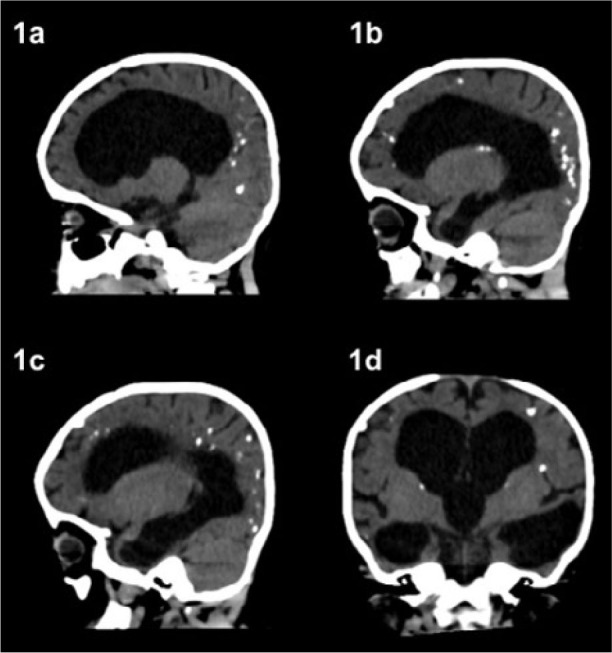

Case description: The mothers had a previous serological diagnosis of toxoplasmosis conducted during prenatal care, with non-reactive (<10 IU/mL) IgM and reactive IgG (>10 IU/mL), and were considered "immune" to the infection. Both infants were born with sequelae of the congenital infection, including neurological and ocular alterations.

Comments: Managing gestational toxoplasmosis in susceptible pregnant women is a considerable challenge in several countries, especially in South America. It is necessary to diagnose and monitor chronic gestational toxoplasmosis, as it may result from reactivation or reinfection. Both forms can cause sequelae and irreparable damage to newborns. In addition, it is essential to guide all pregnant women on how to avoid contact with Toxoplasma gondii, regardless of their serological status.